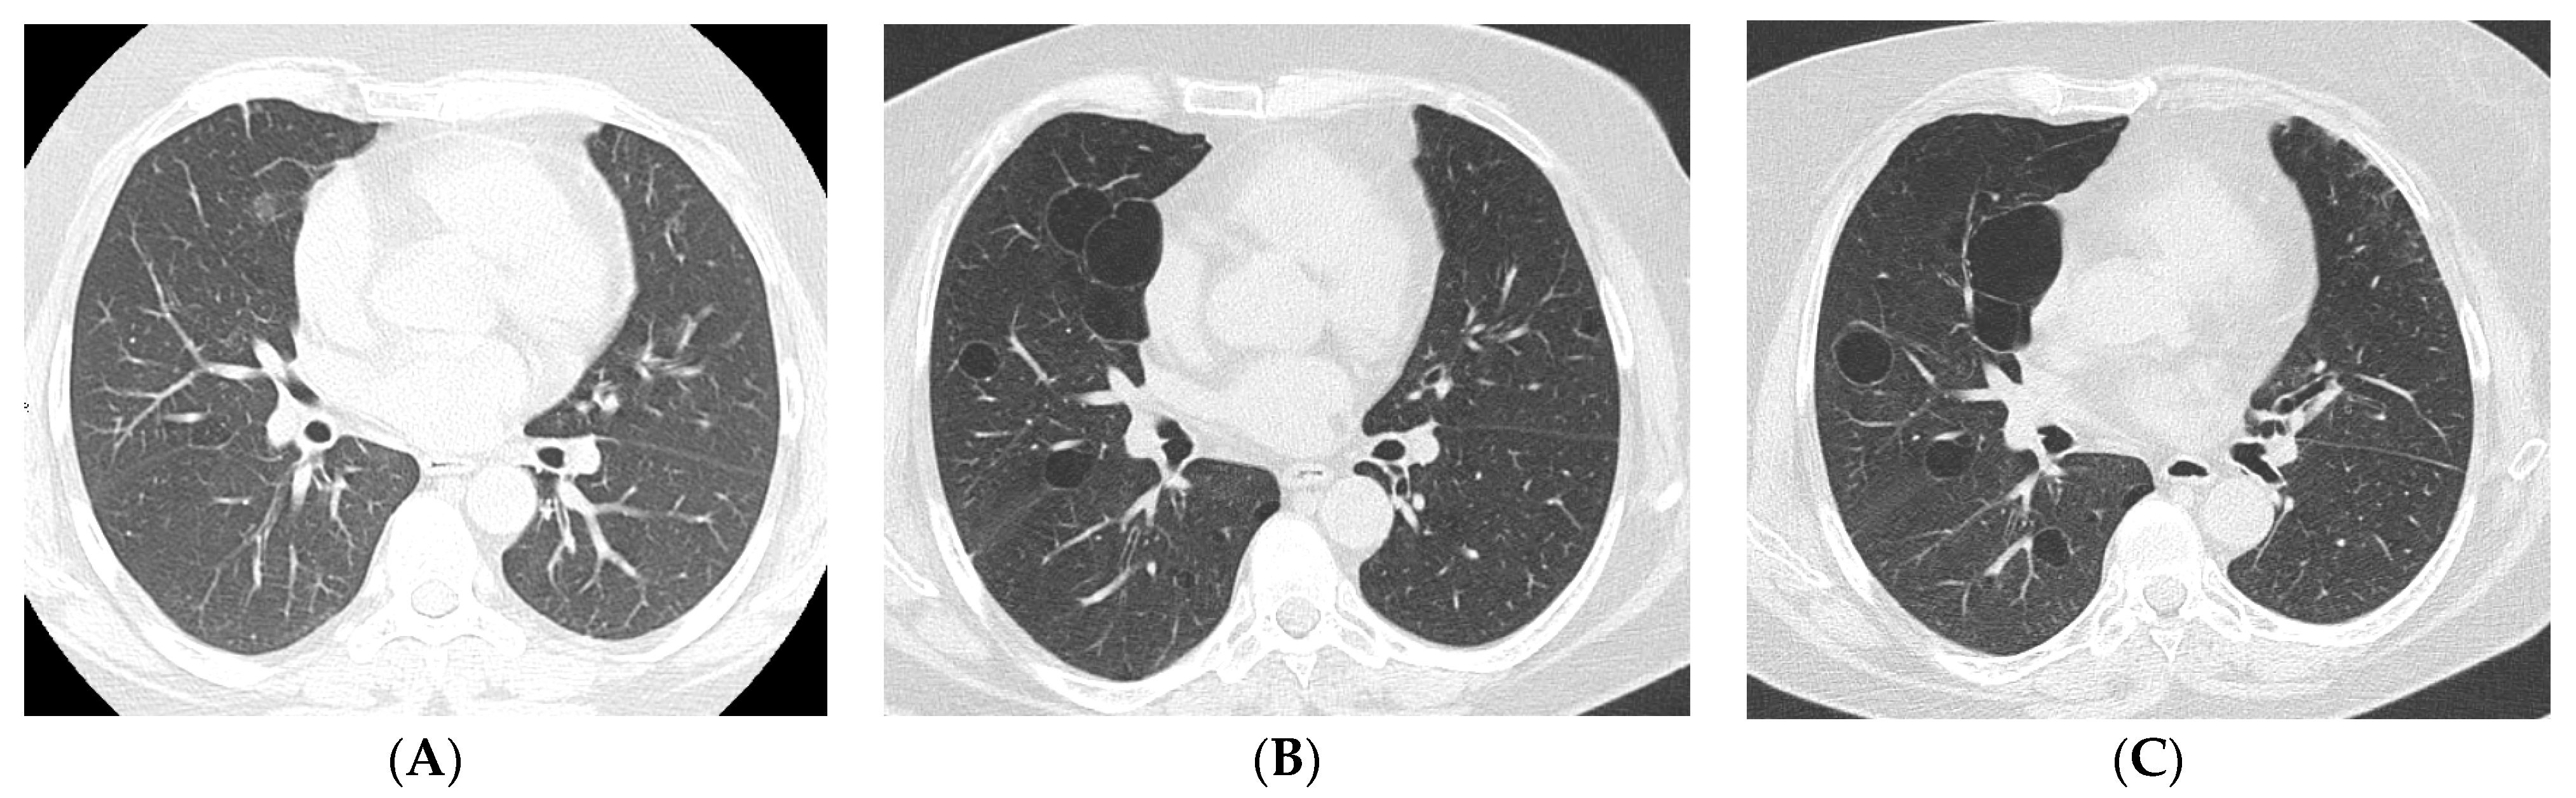

4. Imaging and Histopathology of ILD in pSS

4.1. How Does Radiologic/Histopathologic Pattern Influence the Clinical Picture and Management of pSS-ILD Patients? What Is the Role of Lung Biopsy?